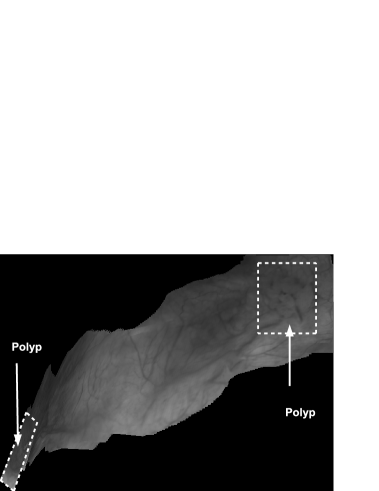

Figures 4 and 5 show two panoramic images constructed from real cystoscopic examination images using and respectively. The panoramic image in Figure 4 is a 1479 1049 pixel image constructed from a 450 image sequence using . In this panoramic image, two polyps are visible on the top-right and at the bottom left of the image. Both polyps can be accurately located in relation to each other. Figure 5 represents a 650 182 pixel panoramic image constructed from a 500 cystoscopic image sequence using . There are no visible discontinuities on texture affirming a quite good visual coherence.

and were programmed in C language using OpenCV vision library. The evaluation of both algorithms robustness and accuracy was done using an Intel Dual core(TM) 2.40GHz, 2Gb RAM computer. The optimization method of the algorithm requires, in average, 250 iterations to register consecutive images. And each image pair registration takes between 50 and 60 seconds. In Figure 5, the construction of the panoramic image took nearly 8 hours 27 minutes. However, in the same experimental conditions, is about 100 times faster than . In fact, a mean number of 12 iterations was needed by the optimization algorithm of the algorithm to register a pair of images. The time of registration for an image pair varied between 0.3 and 0.6 second. The panoramic image shown in Figure 4 was constructed in 3.20 minutes. The computation time of the makes possible the construction of partial panoramic image of the bladder during the standard cystoscopic examination procedure.